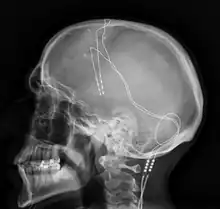

Deep brain stimulation (DBS) is a surgical procedure that implants a neurostimulator and electrodes which sends electrical impulses to specified targets in the brain responsible for movement control. The treatment is designed for a range of movement disorders such as Parkinson's disease, essential tremor, and dystonia, as well as for certain neuropsychiatric conditions like obsessive-compulsive disorder (OCD) and epilepsy.[1] The exact mechanisms of DBS are complex and not entirely clear, but it is known to modify brain activity in a structured way.[2]

The DBS system consists of three components: the implanted pulse generator (IPG), the lead, and an extension. The IPG is a battery-powered neurostimulator encased in a titanium housing, which sends electrical pulses to the brain that interfere with neural activity at the target site. The lead is a coiled wire insulated in polyurethane with four platinum-iridium electrodes and is placed in one or two different nuclei of the brain. The lead is connected to the IPG by an extension, an insulated wire that runs below the skin, from the head, down the side of the neck, behind the ear, to the IPG, which is placed subcutaneously below the clavicle, or in some cases, the abdomen.[9] The IPG can be calibrated by a neurologist, nurse, or trained technician to optimize symptom suppression and control side effects.[36]

DBS leads are placed in the brain according to the type of symptoms to be addressed. For non-Parkinsonian essential tremor, the lead is placed in either the ventrointermediate nucleus of the thalamus or the zona incerta;[37] for dystonia and symptoms associated with PD (rigidity, bradykinesia/akinesia, and tremor), the lead may be placed in either the globus pallidus internus or the subthalamic nucleus; for OCD and depression to the nucleus accumbens; for incessant pain to the posterior thalamic region or periaqueductal gray; and for epilepsy treatment to the anterior thalamic nucleus.

All three components are surgically implanted inside the body. Lead implantation may take place under local anesthesia or under general anesthesia ("asleep DBS"), such as for dystonia. A hole about 14 mm in diameter is drilled in the skull and the probe electrode is inserted stereotactically, using either frame-based or frameless stereotaxis.[38] During the awake procedure with local anesthesia, feedback from the person is used to determine the optimal placement of the permanent electrode. During the asleep procedure, intraoperative MRI guidance is used for direct visualization of brain tissue and device.[39] The installation of the IPG and extension leads occurs under general anesthesia.[40] The right side of the brain is stimulated to address symptoms on the left side of the body and vice versa.